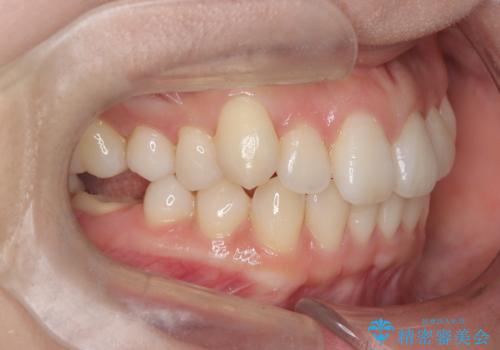

非抜歯矯正で八重歯を改善|短期間8か月で美しい歯並びに|インビザラインライト上顎のみで矯正

- 「八重歯を治したい」との主訴でご来院された患者様です。。

非抜歯で上顎のみインビザラインライトを使用して矯正を行いました。

短期間(約8か月)の治療で歯並びが整い、患者様も大変喜ばれました。